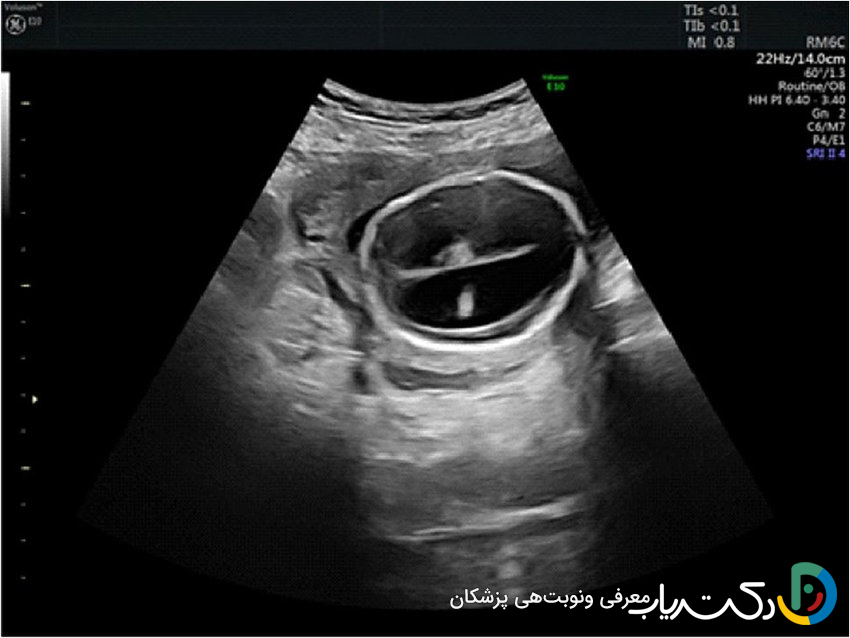

• ونتریکولومگالی: کلیدی‌ترین یافته‌ای که در سونوگرافی شک به هیدروسفالی را برمی‌انگیزد، ونتریکولومگالی یا بزرگ شدن بطن‌های جانبی مغز است. رادیولوژیست عرض دهلیز بطن‌های جانبی را اندازه‌گیری می‌کند.

• اندازه‌گیری طبیعی: کمتر از ۱۰ میلی‌متر.

• ونتریکولومگالی خفیف: بین ۱۰ تا ۱۵ میلی‌متر.

• ونتریکولومگالی شدید: بیشتر از ۱۵ میلی‌متر.

• اهمیت یافته‌ها و علائم مرتبط: تشخیص ونتریکولومگالی همیشه به معنای هیدروسفالی نیست، اما یک زنگ خطر جدی است. متخصص سونوگرافی به دنبال سایر علائم مرتبط نیز می‌گردد، مانند عدم وجود ساختارهای دیگر مغزی (مثل کورپوس کالوزوم) یا ناهنجاری‌های ستون فقرات (مانند اسپاینا بیفیدا). این یافته نیازمند بررسی‌های بیشتر مانند سونوگرافی‌های هدفمند و دقیق‌تر، MRI جنین برای ارزیابی بهتر آناتومی مغز و مشاوره ژنتیک است تا علت زمینه‌ای آن مشخص شود.

تا زمانی که استخوان‌های جمجمه نوزاد به طور کامل به هم متصل نشده‌اند و “ملاج” یا فونتانل قدامی باز است، این “پنجره صوتی” یک راه عالی برای دیدن داخل مغز فراهم می‌کند.

• روش انجام: این روش که سونوگرافی ترانس‌فونتانیل نامیده می‌شود، بسیار ساده است. پزشک مقداری ژل مخصوص را روی ملاج نوزاد قرار می‌دهد و پروب سونوگرافی را به آرامی روی آن حرکت می‌دهد. این فرآیند کاملاً بدون درد و ایمن است و می‌توان آن را در انکوباتور نوزاد نیز انجام داد.

• تصاویر حاصل: سونوگرافی جمجمه به وضوح اندازه و شکل بطن‌ها را نشان می‌دهد و می‌تواند وجود خونریزی ، کیست، آسیب به بافت اطراف بطن‌ها یا سایر ناهنجاری‌های بزرگ را مشخص کند.